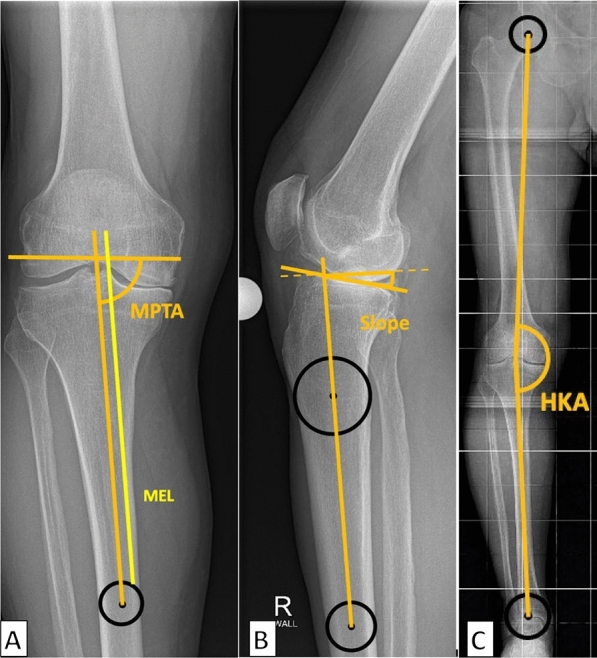

Methods: A total of 2063 patients with medial UKA using the Oxford® mobile partial knee implant were analyzed between July 2014 and September 2022. Various preoperative and postoperative radiographic parameters determining pre- and postoperative alignment and implant positioning, incidence and characteristics of periprosthetic fractures, and patient demographics were assessed. Statistical analyses, including Mann-Whitney U test and logistic regression, were conducted to identify significant associations and predictors of tibial fractures.

Results: Of the 1853 cases that were finally included in the study, 19 (1%) patients experienced TPF. The fracture group presented with a significantly shorter relative mediolateral and posteroanterior distance between the keel and cortex [mediolateral: 23.3% (23.2-24.8%) versus 27.1% (25.7-28.3%), p < 0.001; posteroanterior: 8.4% (6.3-10.3%) versus 10.0% (9.8-10.1%), p = 0.004]. Additionally, an increased posterior tibial slope in pre- and postoperative radiographs [preoperative: 10.4° (8.6-11.1°) versus 7.7° (5.4-10.0°), p < 0.001; postoperative 9.1° ± 3.1° versus 7.5° (5.9-9.0°), p = 0.030] was observed in the fracture group. Furthermore, the use of smaller-sized implants (AA) was associated with higher fracture rates (p < 0.001). Anatomical variants, such as a medial overhanging tibial plateau, were not observed.

Conclusions: In UKA, type Oxford TPF are linked to shorter mediolateral and posteroanterior keel-cortex distances, increased pre- and postoperative PTS, and small implant sizes (AA). Fracture lines often extend from the distal keel to the medial tibial cortex. These findings emphasize the importance of precise implant positioning and sizing to minimize fracture risk. Level of evidence Retrospective single-center study, III.